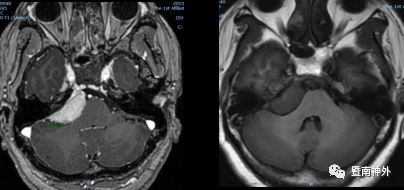

术前影像学检查:

右侧桥小脑角区见一团块状异常信号影,大小约3.6×2.5cm,宽基底,病灶呈等T1WI稍长T2WI信号,DWI呈高信号影,邻近桥脑右侧份受压推移,增强扫描病灶呈明显较均匀强化,可见脑膜尾征。

术后半年复查

本例患者的肿瘤大小为3.6cm×2.5cm,属于内听道前后型CPA脑膜瘤,包绕面、听神经、三叉神经及岩静脉,与脑干关系密切,脑干受压,肿瘤部分长入内听道口,小部分肿瘤通过’ s腔生长中颅窝内;此外,肿瘤宽广基底,血供丰富,此类肿瘤全切除难度较大,是非常有挑战性的一个案例。